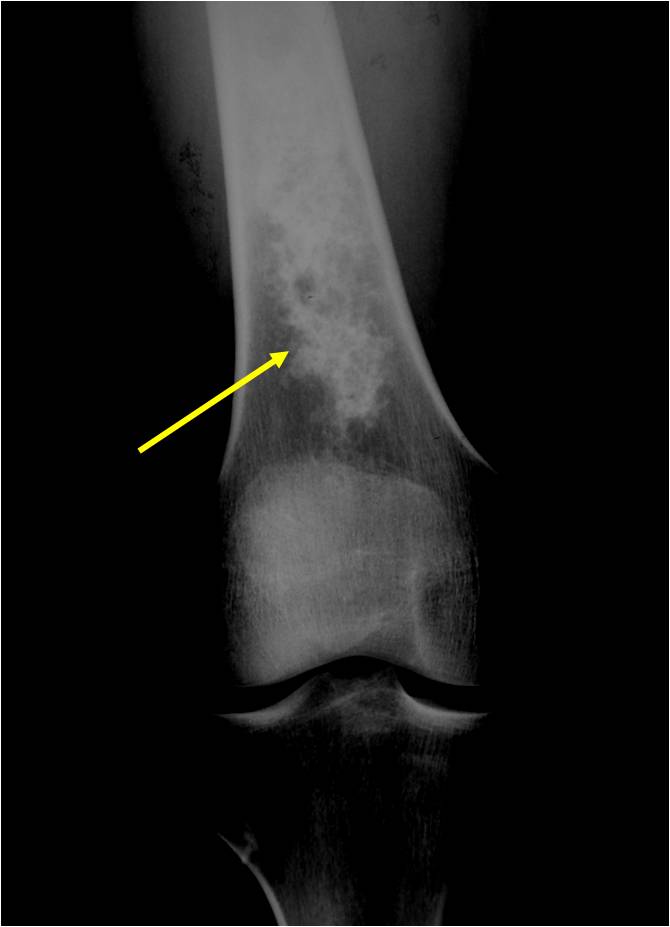

- Localized, radiolucent defect usually with punctate calcifications

- Calcifications are stippled, punctate, popcorn like calcifications and “Ring and Arc” calcifications

- Most commonly found in metaphysis

Plain X-Ray:

- Geographic lytic lesion

- Central often metaphyseal in long bones

- Expansile remodeling with thinned cortex

- Chondroid matrix with calcifications in majority of tumors

Enchondromas in enchondromatosis may involve the metaphysis, diaphysis, epiphysis and articular cartilage